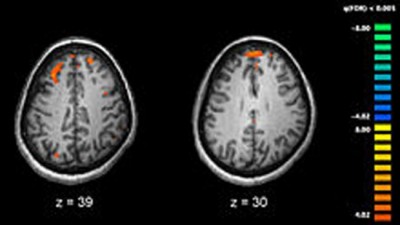

Everyday activities associated with more gray matter in brains of older adults: Study

Feb 27, 2018, at 12:19 am

New York, Feb 26 (IBNS): Higher levels of lifestyle physical activity — such as housecleaning, walking a dog and gardening, as well as exercise — are associated with more gray matter in the brains of older adults, according to a study by researchers in the Rush University College of Nursing. The Journal of Gerontology: Psychological Sciences published the study's findings on Feb. 8.